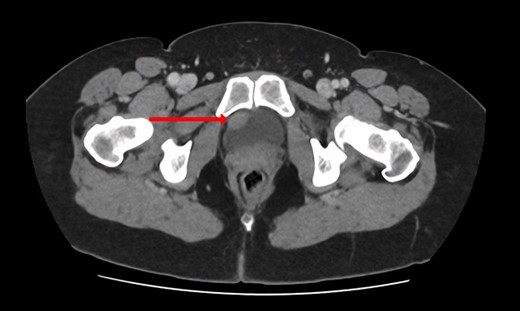

Blood tests included full blood count revealing all parameters within normal limits, eGFR >90 ml/min/1.73m2, Creatinine 64 umol/L and urea 4.5 mmol/L. Urine cultures were negative for infection. Ultrasound revealed a normal-appearing urinary tract, with both kidneys normal in size, shape and echopattern. Flexible cystoscopy revealed only a cystic lesion near the bladder dome which instigated further investigation; subsequent contrast-enhanced Computerized Tomography (CT) abdomen-pelvis scan showed a potential urachal remnant consistent with the flexible cystoscopy finding. In addition, a 1.5-cm-soft tissue structure was identified near the bladder neck which was not clearly seen initially at cystoscopy (Figs 1 and 2).

CT urogram (coronal view) revealing a 1.5 cm thickening at the level of the right lateral bladder neck and a 1-cm-soft tissue thickening at the bladder dome.